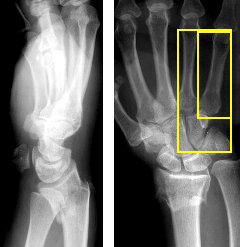

MedVistaGym comprises a set of verifiable medical VQA tasks that demand grounded, multi-step reasoning over visual inputs and intermediate evidence. These tasks span diverse diagnostic scenarios, including clinical perception, lesion-level evidence localization, subtle abnormality detection, and diagnosis-oriented evidence aggregation, where generating reliable answers requires calling external tool support. The training data in MedVistaGym is organized along two complementary axes. (1) Radiology VQA, covering cross-sectional and projection imaging, includes VQA-RAD Lau et al. (2018), which focuses on anatomy and finding recognition in X-ray, CT, and MRI images, and SLAKE Liu et al. (2021), a knowledge-aware dataset with clinically grounded questions over diverse radiology images. (2) Pathology VQA, covering microscopy and histopathology, includes PathVQA He et al. (2020), which emphasizes cellular morphology and tissue patterns. More details are provided in Appendix A.2.